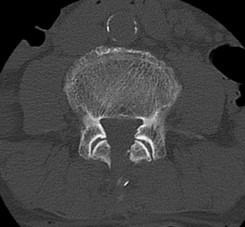

検査

当院では、術前の診断精度を高める目的で、神経根ブロック(左)やCTミエログラフィー(右)検査を行っています。検査後は、経過を確認する目的で1泊入院となりますが、翌日には退院が可能です。